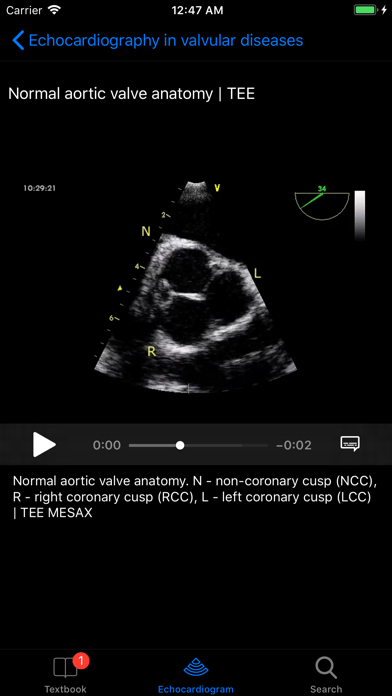

The CARDIO3® ECHOCARDIOGRAPHY project is an app designed as a reference and learning tool for cardiologists, cardiac surgeons, internists, other physicians, and sonographers evaluating echocardiograms for ultrasound diagnosis. The app is edited by Roman Kerekes, MD, Kardio-Vinohradska Cardiology in Prague, Czech Republic. It requires an internet connection and contains 600 annotated videos and growing. Once purchased, the database of videos loading from their server is regularly updated and extended.

1. Great app - I have been waiting for this app! ... lots of interesting videos with detailed legend and high quality, full-resolution echoloops looking great on iPad (and iPhone/iPod -:).

- Contains 600 annotated videos and growing

- Main chapters include Basic Principles, Valvular Heart Diseases, Cardiac Masses and Infective Endocarditis, Pulmonary Embolism and the Right Ventricle Function, Cardiomyopathies and Myocarditis, Diseases of the Aorta, Diseases of Pericardium, Congenital Heart Diseases in the Adult, and Cases